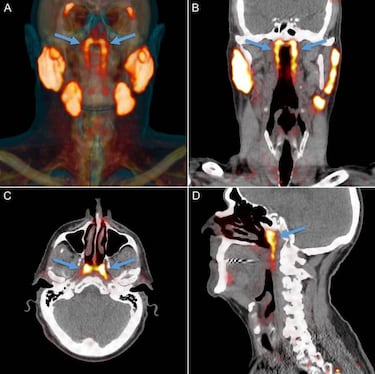

Este conjunto de glándulas salivares se encuentra escondido en nuestra cabeza y fue descubierta por pura casualidad, cuando se le realizaban pruebas a diferentes pacientes con un escáner avanzado llamado PSMA PET / CT. Y es que, combinado con inyecciones de glucosa radiactiva, que sirva para que se resalten los tumores en el cuerpo al realizar las pruebas, mostró estas glándulas en la parte posterior de la nasofaringe.

Este descubrimiento podría tratarse del cuarto conjunto de glándulas salivares que tenemos en nuestra cabeza. Están ubicadas detrás de la nariz y sobre el paladar, más o menos en el centro de nuestras cabezas. Matthijs Valstar, primer autor del estudio, de la Universidad de Amsterdam declara “las dos nuevas áreas que se iluminaron resultaron tener otras características de las glándulas salivales también. Las llamamos glándulas tubarias, refiriéndonos a su ubicación anatómica”.

Estas glándulas se observaron gracias a la tecnología avanzada en exámenes clínicos de los 100 pacientes que participaron en el estudio. Además, también se hicieron investigaciones en dos cadáveres, uno masculino y otro femenino. Expertos apuntan que este descubrimiento no ha llegado antes por “la ubicación anatómica de difícil acceso de las estructuras”, y es que se encuentran debajo de la base del cráneo. Sin embargo, en estos estudios se observó esta “misteriosa estructura” que reveló aberturas de los conductos de drenaje macroscópicamente visibles hacia la pared nasofaríngea.